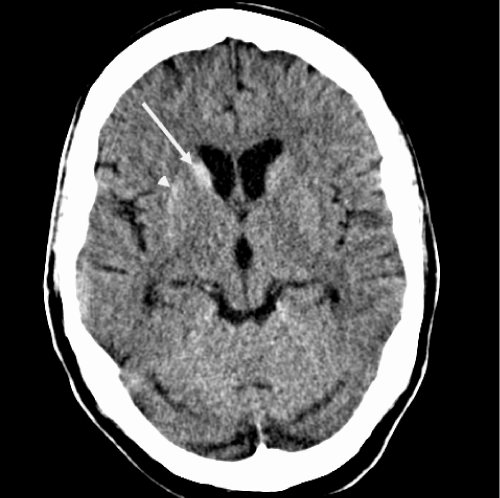

Figure 1: Initial CT scan at presentation to the Emergency Department at our

institution. Axial CT scan at the level of the basal ganglia. There is increased

density of the right caudate nucleus head (long arrow) and subtle increased

density of the lateral aspect of the right putamen (short arrow). The right

lentiform nucleus may be slightly smaller than the left. The hyperdensity could

represent mineralization or possibly blood

Unenhanced CT head revealed increased density in the head of right caudate nucleus and subtle increased density in the lateral aspect of the right putamen. The right lentiform nucleus appeared smaller than the left. Contrast enhanced brain MRI revealed T1 shortening (hyperintensity) within the head of the right caudate nucleus and putamen, which was more pronounced along the lateral aspect. The axial T2-weighted image revealed subtle hyper intensity in the putamen while the caudate head had a normal signal. Vascular imaging was unremarkable. His hemoglobin A1C was 12.7 % and plasma osmolality was 301mOsm/kg (checked after he was hydrated in the emergency department). The provisional diagnosis was HBHC due to non-ketotic hyperosmolar hyperglycemia.